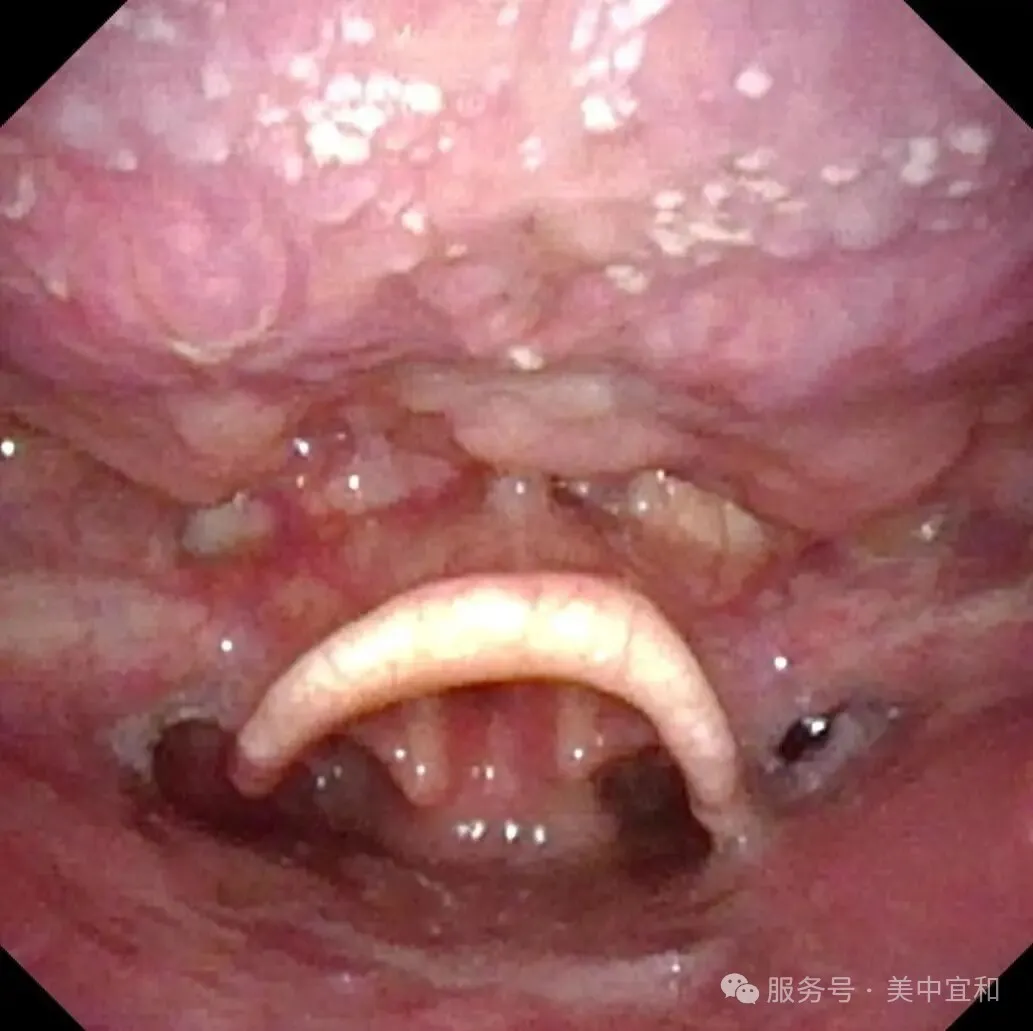

从消化内科无缝衔接到耳鼻喉科,由于疑似肿物位于喉腔入口处的会厌部,王主任马上为C先生安排了更为精细的电子鼻咽喉镜检查 ,确诊为会厌侧乳头状瘤。

会厌左侧缘乳头状瘤

王主任提到,这种肿瘤绝大多数为良性病变,生长速度相对缓慢,恶变的风险较低,但存在播散到其他黏膜的可能。若不及时治疗,肿瘤可能累及并扩散至声带等部位,可能出现咽喉异物感,吞咽不适、声音嘶哑,严重时肿瘤会阻塞喉腔入口,还可能引起呼吸困难,增加了治疗难度,甚至需要做气管切开。所幸发现及时,C先生肿瘤病变还未波及到声门以下,王主任建议手术治疗,采用支撑喉镜下微创手术,通过喉镜暴露肿瘤后,使用低温等离子将肿瘤完整切除,这种术式创伤小,可以最大限度地保留会厌部的正常功能,并且有助于恢复。最终手术顺利完成,用时20分,出血量仅1ml。